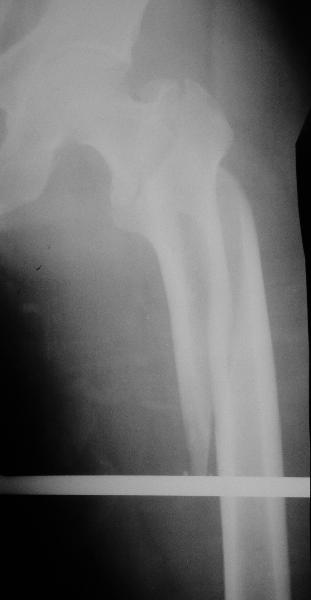

Второй случай тоже репозиция из малого доступа, больному 19 лет, множественные огнестрельные повреждениия конечностей, живота и черепа, правая конечность холодная, без пульсации. Ортопедический диагноз: огнестрельный перелом правого бедра. При срочной ангиографии повреждения сосудов не подтвердилось, конечность из-за ургентности состояния больного зафиксирована временным наружным фиксатором и больной оставлен на операционном столе для срочной лапаротомии хирургической службой.

Больной долго оставался нестабильным, только на 14 день удалось заменить на антеградный интромедуллярный штифт TFN (trochanteric femoral nail) SmithNephew. После неудачной попытки закрытой репозиции, несмотря на использование "joystick", проксимальный стержень от

наружного фиксатора, (перелом начал срастаться) репозицию провели из малого доступа, затем остальные этапы операции.

Случай был представлен из-за того, что больного оперировали после наружной фиксации и был риск инфекцирования через места проведения стержней (на снимках), прошло больше 3 месяцев, выписан из амбулаторной службы из-за отсутсвия надобности дальнейшего наблюдения.